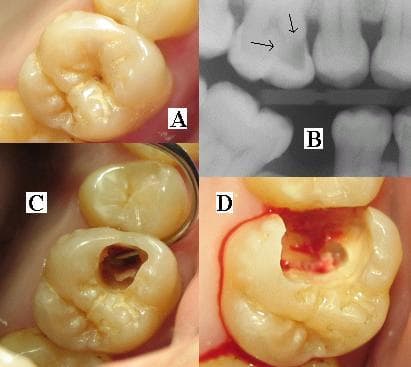

Because you are paying directly, the gap between a good clinic and a bad one hits you in two ways: your mouth and your wallet. A poorly placed implant can require CHF 4,000–6,000 in corrective surgery. A missed caries lesion on an X-ray can turn a CHF 250 filling into a CHF 1,800 root canal within 18 months. The stakes are real and choosing well the first time is the single highest-ROI decision you can make as a Geneva resident.

Digital radiography has been the standard in Switzerland since the early 2000s. It emits roughly 90% less radiation than analogue film. A clinic still using film-based X-rays in 2026 is behind the curve. More importantly, your X-rays belong to you under Swiss data protection law. Any dentist who refuses to give you a copy is hiding something.

Suggesting extractions when alternatives exist

Modern endodontics (root canal treatment) saves 85–95% of teeth that used to be extracted. If your dentist jumps to extraction for a painful molar without considering RCT, get a second opinion from an SSO specialist in endodontology.